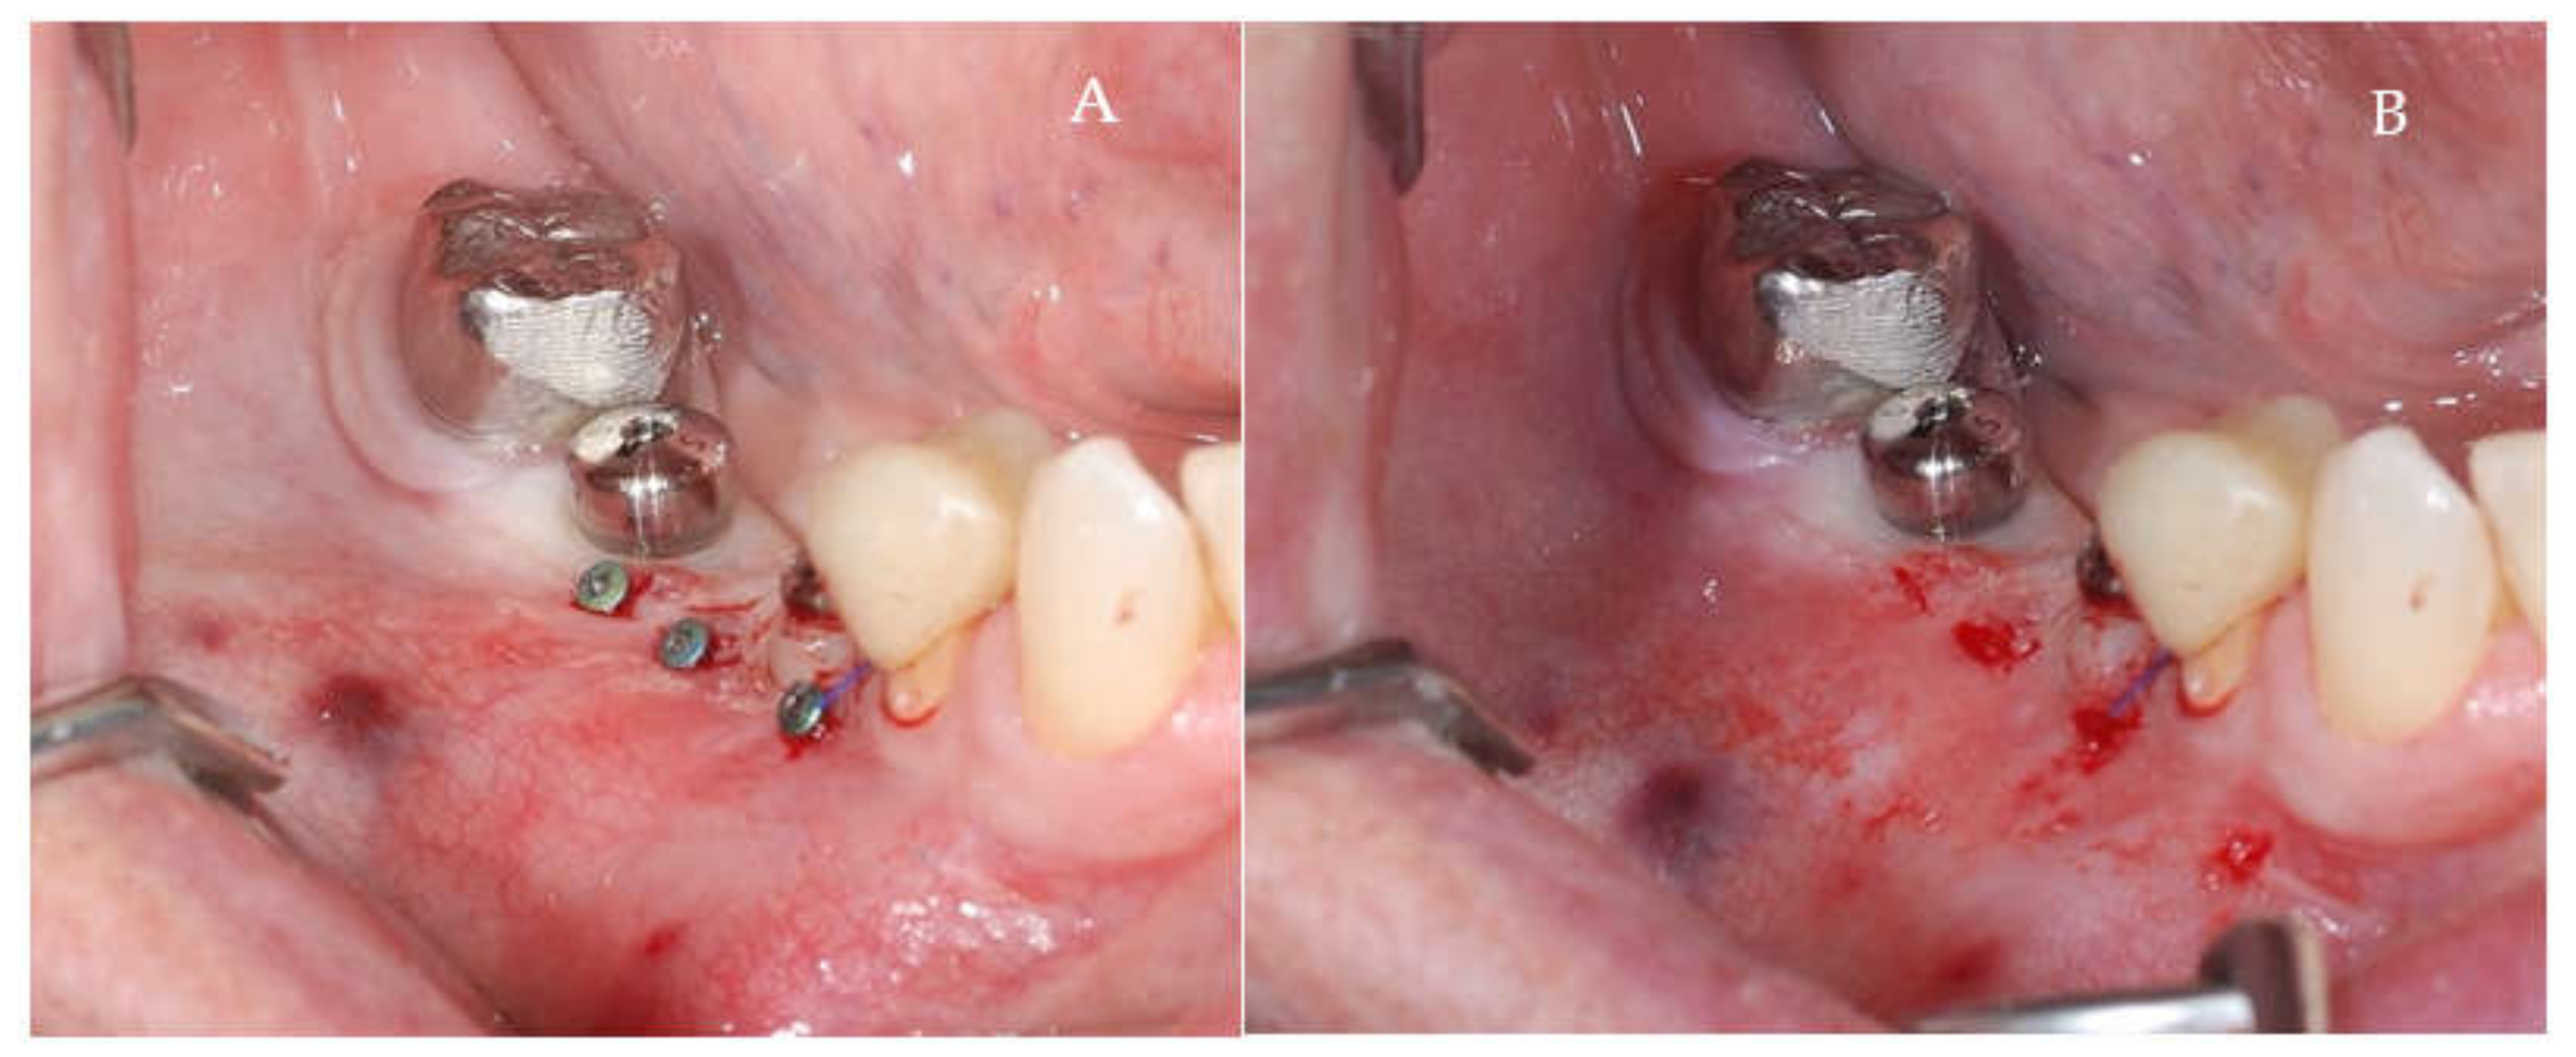

Clinical and CBCT aspects of patient from the test group, describing the stages of S-GBR technique and implant-prosthetic stage, are presented in Figure 1, Figure 2, Figure 3, Figure 4, Figure 5, Figure 6, Figure 7, Figure 8, Figure 9, Figure 10 and Figure 11. CBCT exam allows the evaluation of the horizontal alveolar bone defect and the position of the mandibular alveolar nerf (Figure 1A,B). Figure 1C,D show cross-sectional CBCT aspects of the implant sites. Figure 2 shows the narrowed mandibular alveolar bone with horizontal resorption. Figure 3 shows the exposed buccal surface of the alveolar ridge with severe horizontal resorption, after flap opening. The inserted implants (4.5 mm diameter, 11.5 mm length) and osteosynthesis screws (45° from the occlusal plan) are shown in Figure 4A. The placement of graft (autologous bone and xenograft) and collagen membrane is shown in Figure 4B. Figure 5A shows tension-free sutures, due to periosteal incisions alveolar ridge. Figure 5B shows clinical aspect at 7 months after surgery, with gingival tissue adherent on the reconstructed alveolar ridge. Figure 6 shows OPG aspect at follow-up of 7 months, with osseointegration of the dental implants. Figure 7A shows clinical aspect before osteosynthesis screws removal. Figure 7B shows clinical aspect after osteosynthesis screws removal. Figure 8A shows healthy peri-implant soft tissues. Figure 8B shows repositioning key for perfect position of abutments. Figure 10A,B show clinical aspects of implant-supported prosthetic restoration. Figure 11A,B show CBCT aspects of Osseo integrated dental implants at 24 months follow-up.

Figure 9.

(A,B) Post-operative clinical aspects 3 weeks after second stage surgery. (A) Healthy peri-implant soft tissues (B) The repositioning key of abutments.